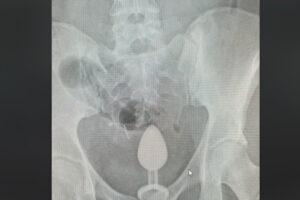

2023 11.09 病院に運ばれた女性の下腹部レントゲンに、お尻の栓が写ってしまう 国際ニュースまとめ 親しい男性とちょっと怪しいプレイをしていた34才のイギリス人女性。お尻に入れた大人のおもちゃが出てこなくなり、夜間救急外来に助けを求めることになった。海外メディアが記事として取り上げている。 Source: Switch News もっと記事を見ていきませんか? マックで飲むコーラの味が、普通と違うのには理由があった! バンコクでのNintendo SwitchイベントにBNK48とPROXIE 新しい学校のリーダーズ、おとぼけビ〜バ〜ら出演決定!タイ・バンコクの音楽フェス「Maho Rasop 2023」 セガ、 「タイランドゲームショウ」に初出展 【タイ】水に浸かりながら食べるお店、お客が集まり人気スポットに 意外と怖い…米でハロウィーン屋敷のコンテスト、家の前にさまざまな幽霊が並ぶ Tweet Share Hatena Pocket Post navigation 前の記事 次の記事 関連記事 コストコがトランプ政権提訴 なぜ 台湾当局「中国軍が海峡で模擬攻撃」 外国艦船を追跡… 2026年 タイ祝日・休日カレンダー 朝日新聞社・石合編集委員に韓国のメディア賞 朝鮮通… 本当に“日本版トラスショック”は生じないのか 獲物を狙うサメや人の顔の形をした火山噴火――国際航… タイ、数十年続いた午後の酒販売禁止を一時解除 J.Y.Parkが沖縄に家族旅行→娘2人との動画も… 【Wミリオン】両学長『お金の大学』は、なぜ&…